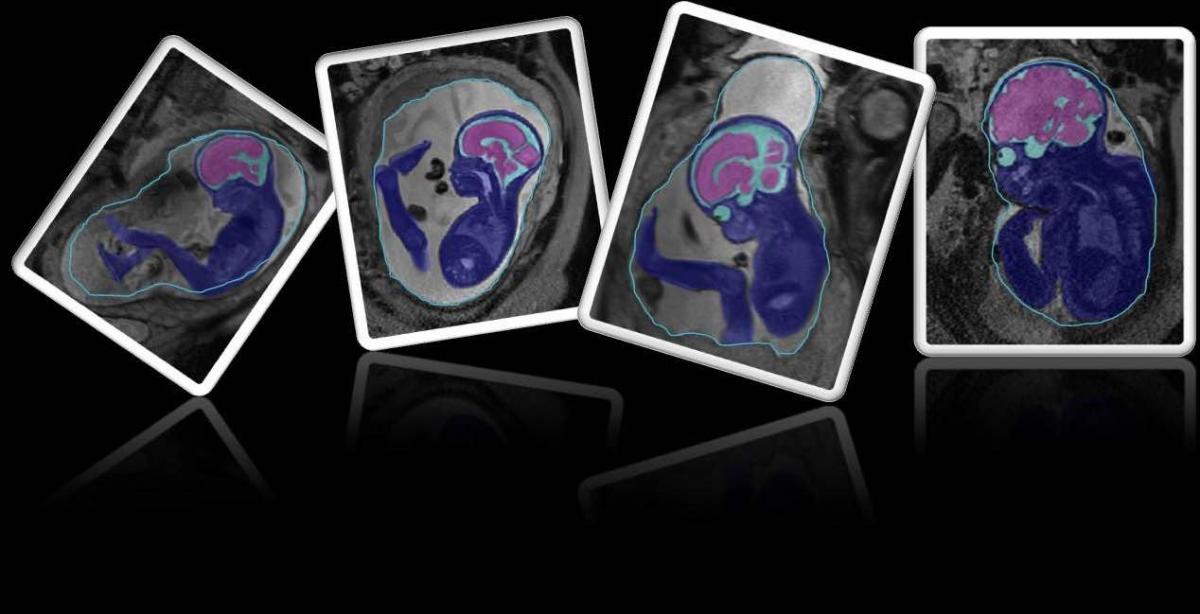

A technika világa egyre gyorsabban fejlődik és már olyan dolgokra képes, amit néhány évvel ezelőtt nem is hittünk volna el. Az új technológiának köszönhetően a gépekkel a terhességet is jobban nyomon tudjuk követni. Ezzel foglalkozik többek között az iFind nevű projekt is.

David Lloyd kutató orvos szerint az új technikai vívmányok segítenek a még meg nem született kisbabák betegségeinek kimutatásában. Különböző technológiát és ultrahang készülékeket felhasználva kiváló diagnosztikai képet adó gépeket fejlesztettek ki az utóbbi időben.

A filmben szereplő édesanya is részt vesz a projektben. David Lloyd elmagyarázza, hogy az ilyen típusú felvételeknél az egyetlen hátrány az, hogy a magzat szinte állandóan mozog. Ezt nagyon jól láthatjuk a felvételen.

Hihetetlen, hogy a terhesség korai szakaszában már ilyen részletes felvételt lehet készíteni a modern gépek segítségével. Az pedig csodálatos, hogy láthatjuk mennyit mozog egy ilyen apróság!Mintha fel akarna kelni!